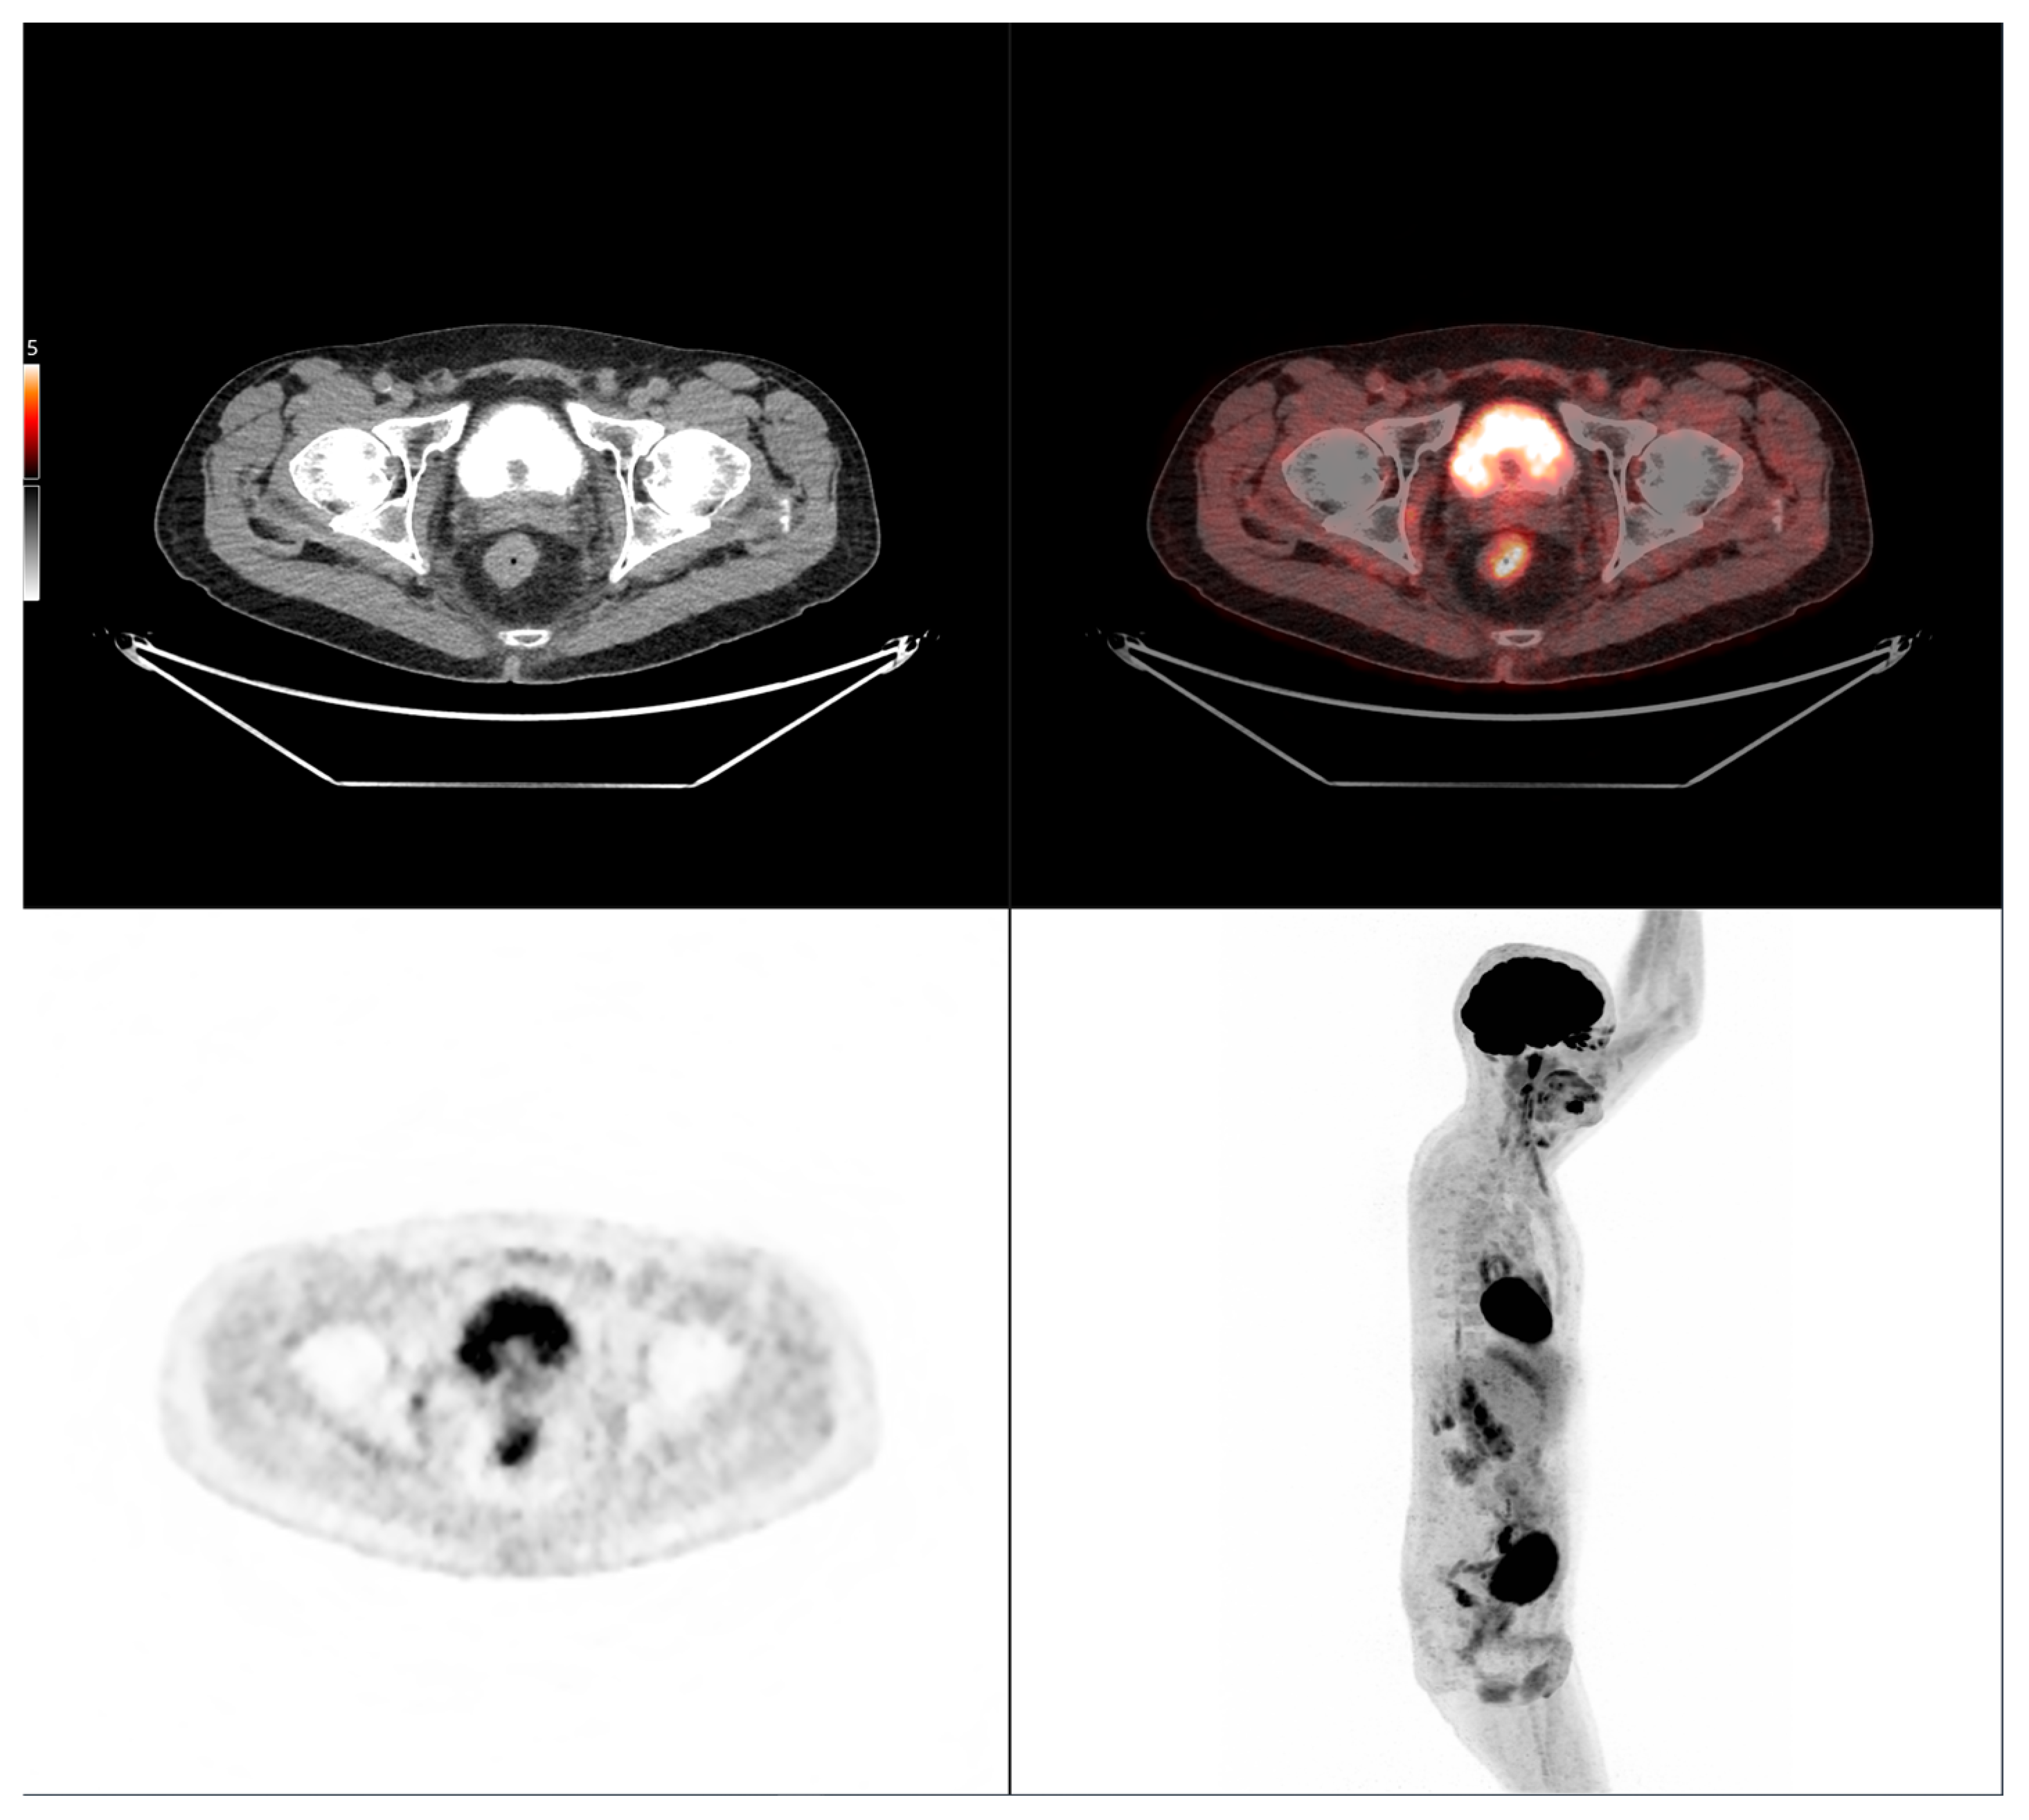

Altogether, these analyses demonstrate that MTV of the primary tumor is a consistent predictor of both OS and PFS. While OS was primarily influenced by sex and MTV, PFS was more strongly determined by UICC stage and MTV, as displayed in Figure 6. For a clearer understanding of the presented results, Figure 7 shows a representative example of manual delineation of the primary tumor on baseline FDG PET/CT.

Figure 7.

Representative example of manual delineation of a primary rectal tumor on baseline FDG PET/CT showing manual delineation of the metabolically active tumor volume (first row) on the PET image with corresponding fused PET/CT image and CT image with iodinated contrast medium (second row). Morphological features, including tumor shape (circular or semi-circular), cranio-caudal extension (in cm), and overall tumor volume (in cm3), were assessed on the CT image (often with contrast medium) coregistered with the PET images. Tumor shape was determined on the axial plane, cranio-caudal extension on the sagittal plane, and tumor volume after careful delineation on all planes. Iodinated contrast medium was administrated in 70% of cases after exclusion of contraindications. Metabolic parameters, including SUVmax, SUVmean, MTV and TLG, were systematically extracted from the segmented tumor (yellow in this figure). SUVmax (M in this figure) and TLG were automatically displayed. SUVmean could be obtained by simply replacing SUVmax with SUVmean in the parameter selection. MTV was automatically calculated from TLG and SUVmean values displayed on the workstation. The highlighted region in yellow represents the 3D contour of the primary tumor, excluding physiological uptake and non-tumor regions.

Case 1: An 80-year-old patient with stage IVA rectal cancer and synchronous anal carcinoma, presenting with a large circumferential primary tumor showing a craniocaudal extension well above the predictive cut-off (13.0 cm vs. 6.2 cm; volume: 79.2 mL) and a metabolic tumor volume markedly exceeding both prognostic thresholds (MTV 79.0 vs. 35.49 for OS and 32.08 for PFS). Baseline FDG PET/CT demonstrates locoregional nodal involvement and a solitary liver metastasis in segment VII. The patient experienced rapid disease progression, with a progression-free survival of 8 months and an overall survival of 27 months.